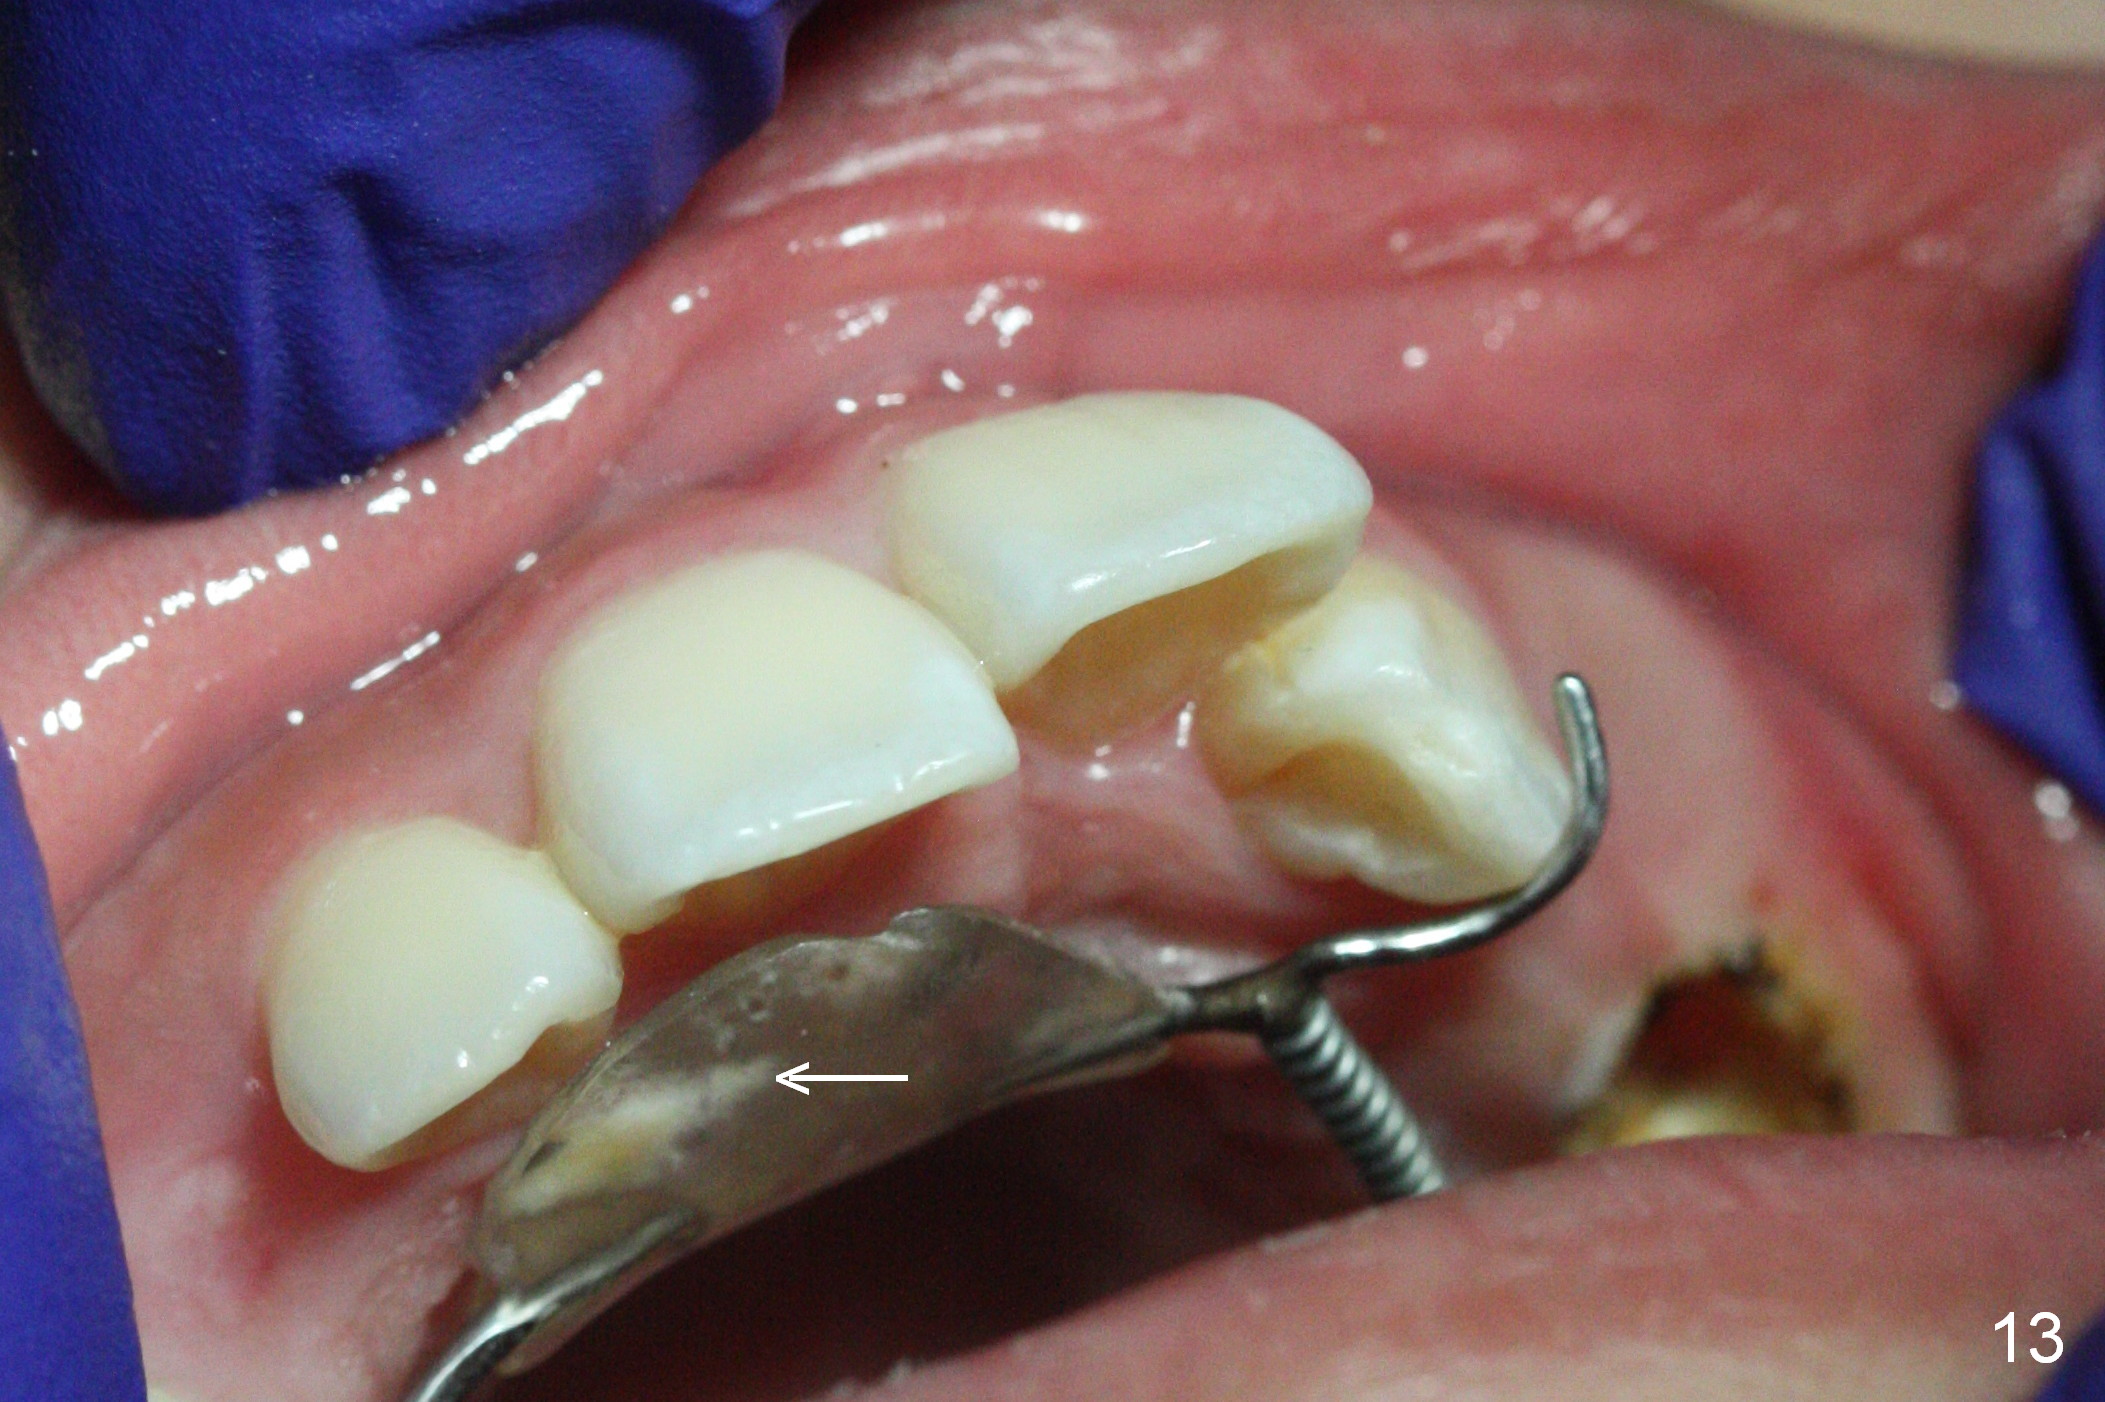

Nearly 2 months post regainer placement, UL6 appears to have been distalized (Fig.11 arrow), but UL4,5 have not erupted (Fig.12), while UL1,2 are displaced (Fig.13). Diode laser is used to expose the tooth buds, which are deeply seated (Fig.14). If they do not erupt soon, a mini implant should be placed for anchorage (Fig.10). Use several power chains to retract the anterior arm, while drill through the Nance appliance (high speed handpiece) for mini implant placement.